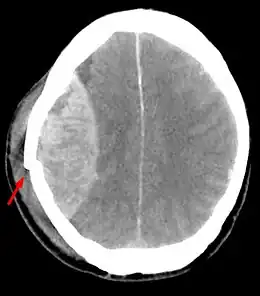

Aspect tomodensitométrique d'un hématome extradural

La tomodensitométrie cérébrale sans injection de produit de contraste confirme le diagnostic et permet de noter des :

1. Signes directs : hyperdensité spontanée en lentille biconvexe[2]. Elle précise les caractéristiques de l’hématome : siège, étendue, retentissement de l'hématome sur le cerveau. (effet de masse sur les ventricules) ;

2. Signes indirects : refoulement d’un ventricule[2], déplacement d’un plexus choroïde, déplacement de la ligne médiane ;

3. Lésions associées[2] : hypodensité piqueté de flaques hémorragique hyperdenses : attrition sous-jacente, un corps étranger.